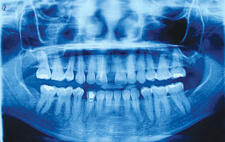

O.P.G.

We have O.P.G. or full mouth X-Ray facility for early diagnosis as well as for treatment of peridontal disease. It is also used to assess the bone loss level, endodontics, implantology, etc.